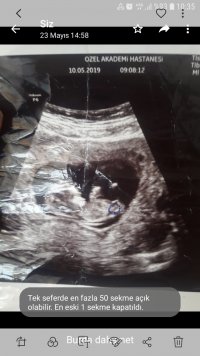

13+2 nub değerlendirir misnz acaba dr foto wermedi bunlar bnm çektiğm fotolar